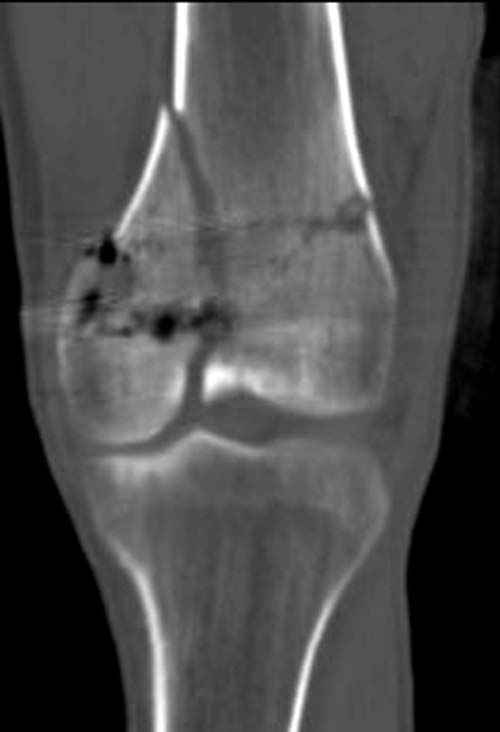

По Густило и Андерсену все high-energy переломы являются III не зависимо от степени повреждения мягких тканей. Plating такого перелома на второй день кажется немного рискованным хотя "победителей не судят". Судя по КТ, медиальный мыщелок стабильный, насколько необходимо было его фиксировать?

Красиво и быстро?! - две пластины + 18 шурупов.

Идеальная репозиция?! -На снимочке A-P проeкции видна "зазубрина" по суставной поверхности, латеральный снимок - тоже не идеально.

Множество мелких FB в кости.